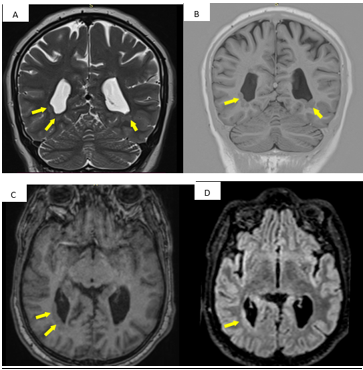

A Rare Association between Congenital Strabismus and Cortical Malformations: MRI Evidence of Grey Matter Heterotopia

Jabour Soukayna, Lahfidi Amal, Elaitari Khadija, Boujida Nadia, Khamlichi Amina, Fikri Meriem, Toursa Firdaous, Echcherif Kettani Najwa and Jiddane Mohamed